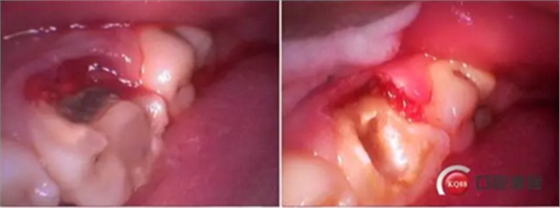

牙列完整,后牙中性關(guān)系,前牙開合,中線對(duì)齊。16合面大面積齲壞,內(nèi)褐色腐質(zhì),冷診無反應(yīng),叩痛(+-)。36合面樹脂充填,充填物在位,頰側(cè)冠折,折線位于齦緣下,冷診無反應(yīng),叩痛(+)。其他無殊。

診斷:36冠根折。

這是折線的位置,右是拔出的牙齒碎片。很明顯折裂波及遠(yuǎn)中頰根。